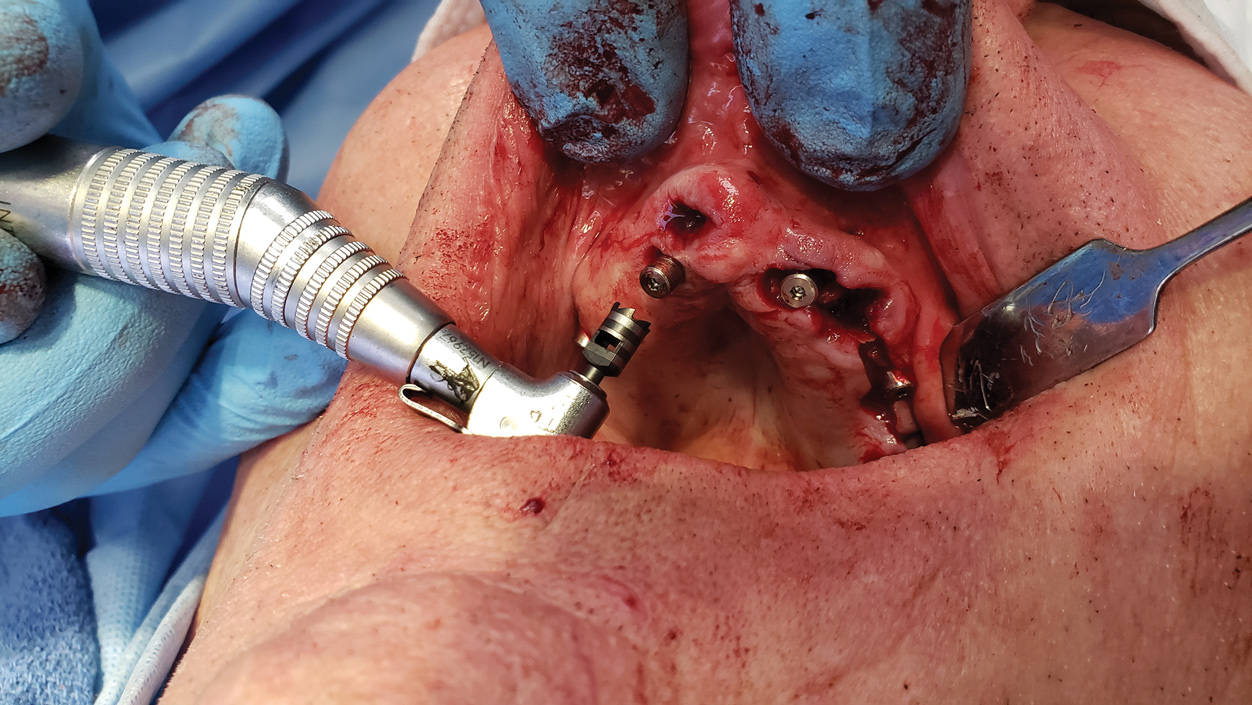

The second patient appointment includes any planned extractions and the surgical placement of implants using dynamic navigation that follows the virtual implant plan (Figure 8). After the implants are placed, any planned alveoloplasty is made using the implant shoulders as the guide for the reduction. Bone mill guides can be installed to protect the implant connection during the reduction. Any planned transmucosal abutments are connected. Temporary copings are also connected (Figure 9). The conversion denture is tried in to confirm that copings are positioned in the premilled openings in the conversion denture (Figure 10 and Figure 11). Using the occlusal locks and positioning handle, the temporary copings are picked up while the patient is set into static occlusion using autopolymerizing resin. After the resin is cured, the conversion denture is unscrewed from the patient and refined chairside. The soft tissue flaps are sutured, and the finished, polished conversion prosthesis is delivered (Figure 12 and Figure 13).

Figure 8: Dental implant is ready for installation with dynamic navigation in the mandible.

Figure 8

Figure 9: Titanium temporary cylinders that will become part of the conversion prosthesis are placed on transmucosal abutments.

Figure 9